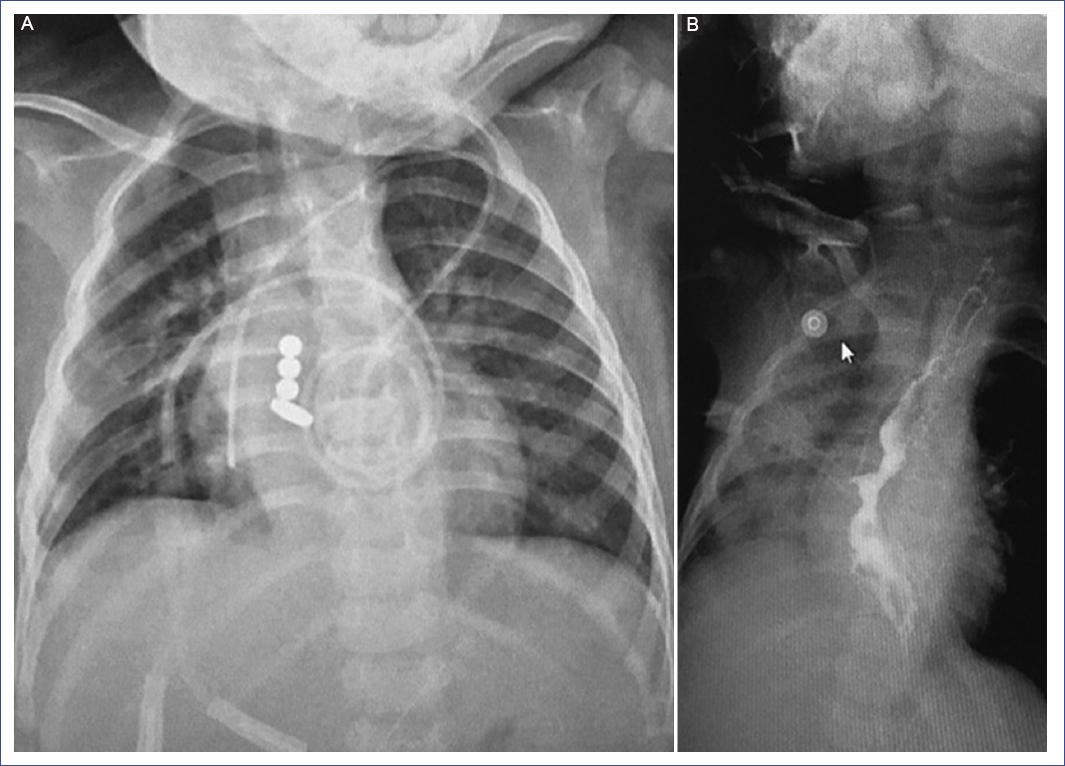

Al año y 7 meses de edad se colocaron imanes en el cabo ciego esofágico y el cabo ciego del estómago por endoscopia. La paciente cursó con un nuevo evento de sepsis con foco pulmonar, por lo que recibió ventilación mecánica y antibióticos de amplio espectro. Se realizó un esofagograma 2 meses después de la colocación de los imanes y se documentó el paso del contraste del esófago al estómago con un calibre disminuido (Fig. 1). Se realizó una endoscopia, durante la cual se logró pasar un hilio para iniciar las dilataciones esofágicas con dilatadores tipo Tucker y se instituyó la alimentación enteral por vía oral. La paciente egresó con tolerancia de la vía oral; las dilataciones esofágicas se siguieron aplicando de manera mensual hasta llegar a introducir una sonda Tucker 34 Fr sin eventualidades.

Figura 1 A: radiografía simple de tórax en la cual se observan los imanes colocados en los cabos ciegos en el esófago y el estómago. B: se aprecia una disminución del calibre con el paso del contraste.